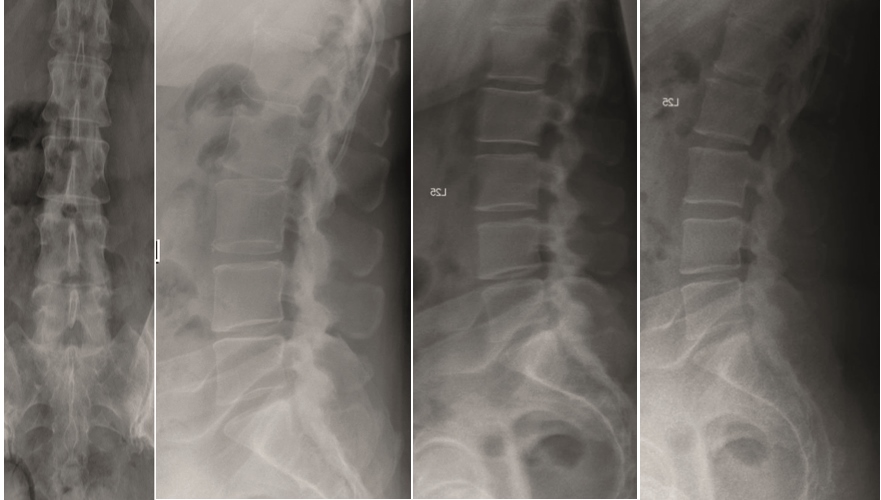

A 45-year-old healthy male patient experienced load dependent lower back pain (LBP) for 6 years, with no radicular pain and no neurologic deficit.

Multilevel facet pathology is shown in Fig 6. Intraoperative and postoperative images are shown (Fig 7-9).